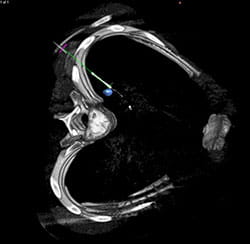

The room is equipped with all of the advanced radiology technology a surgeon may need. This includes X-ray, fluoroscopy (live X-ray), ultrasound and computed tomography (CT). Surgeons work side by side in the hybrid OR with interventional radiologists, who specialize in using these imaging technologies.

Imaging can be performed in the hybrid OR just before the surgery to help plan the procedure, during the surgery to identify important anatomy or disease, and after the surgery to evaluate results. In some situations, the surgeon will pull up images taken prior to surgery and overlay them with images taken in the hybrid OR. This can provide important details and help improve safety and accuracy.

In addition, the technology can help surgeons see their surgical tools as they navigate them inside the patient’s body. This improves surgical accuracy and helps surgeons avoid critical structures.